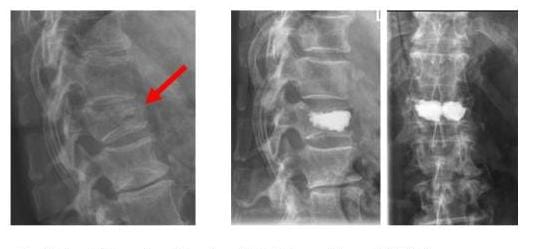

KYPHOPLASTIE

Röntgenbild links zeigt einen Wirbelkörpereinbruch rechts der Wirbelkörper wurde mit Zement aufgefüllt und so stabilisiert

Die linke Bild zeigt einen Wirbelkörpereinbruch (Pfeil). Der Wirbelkörper wurde mit Zement aufgefüllt und so stabilisiert (rechte Bilder). (Bilder: Orthopädie)